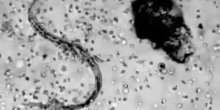

Svake sekunde naše tijelo se tiho bori protiv infekcija i bolesti. Ovaj moćni proces prvi put je zabilježen na timelapse snimku i otkriva koliko su agresivna naša bijela krvna zrnca, prenosi b92.